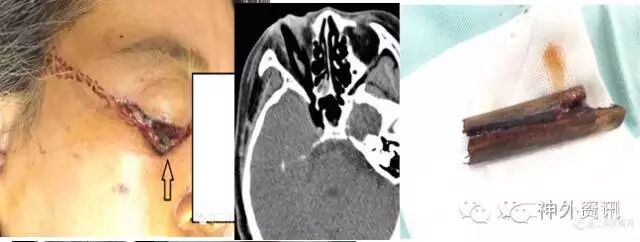

入院查体:神志模糊,烦躁,GCS11分,双侧瞳孔等大等圆3mm,对光反射灵敏,右侧颌下可见约2cm伤口,内可见离断的螺纹钢残端,左侧额颞皮下凸起,可触及皮下的另一残端(见图1黄色箭头)。口鼻腔少量出血。

图1. 右侧颌下可见约2cm伤口,内可见离断的螺纹钢残端,左侧额颞皮下凸起,可触及皮下的另一残端(黄色箭头)。

图12. 刀片插入眶颅,顺利拔除(患者,女,67岁)。